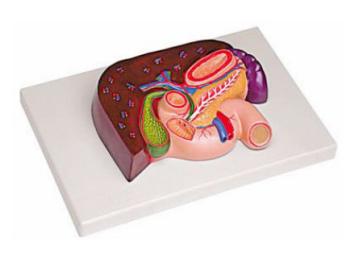

肝、胰、脾、十二指肠、胃模型

肝、胰、脾、十二指肠、胃模型